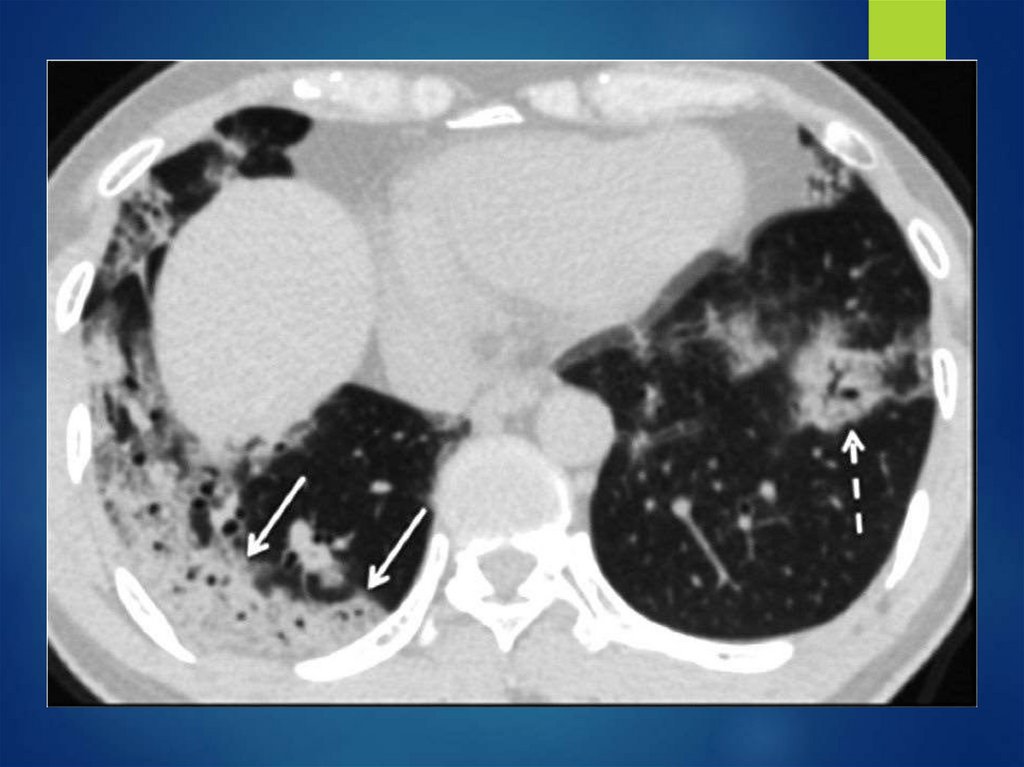

МТС рака щитовидной железы